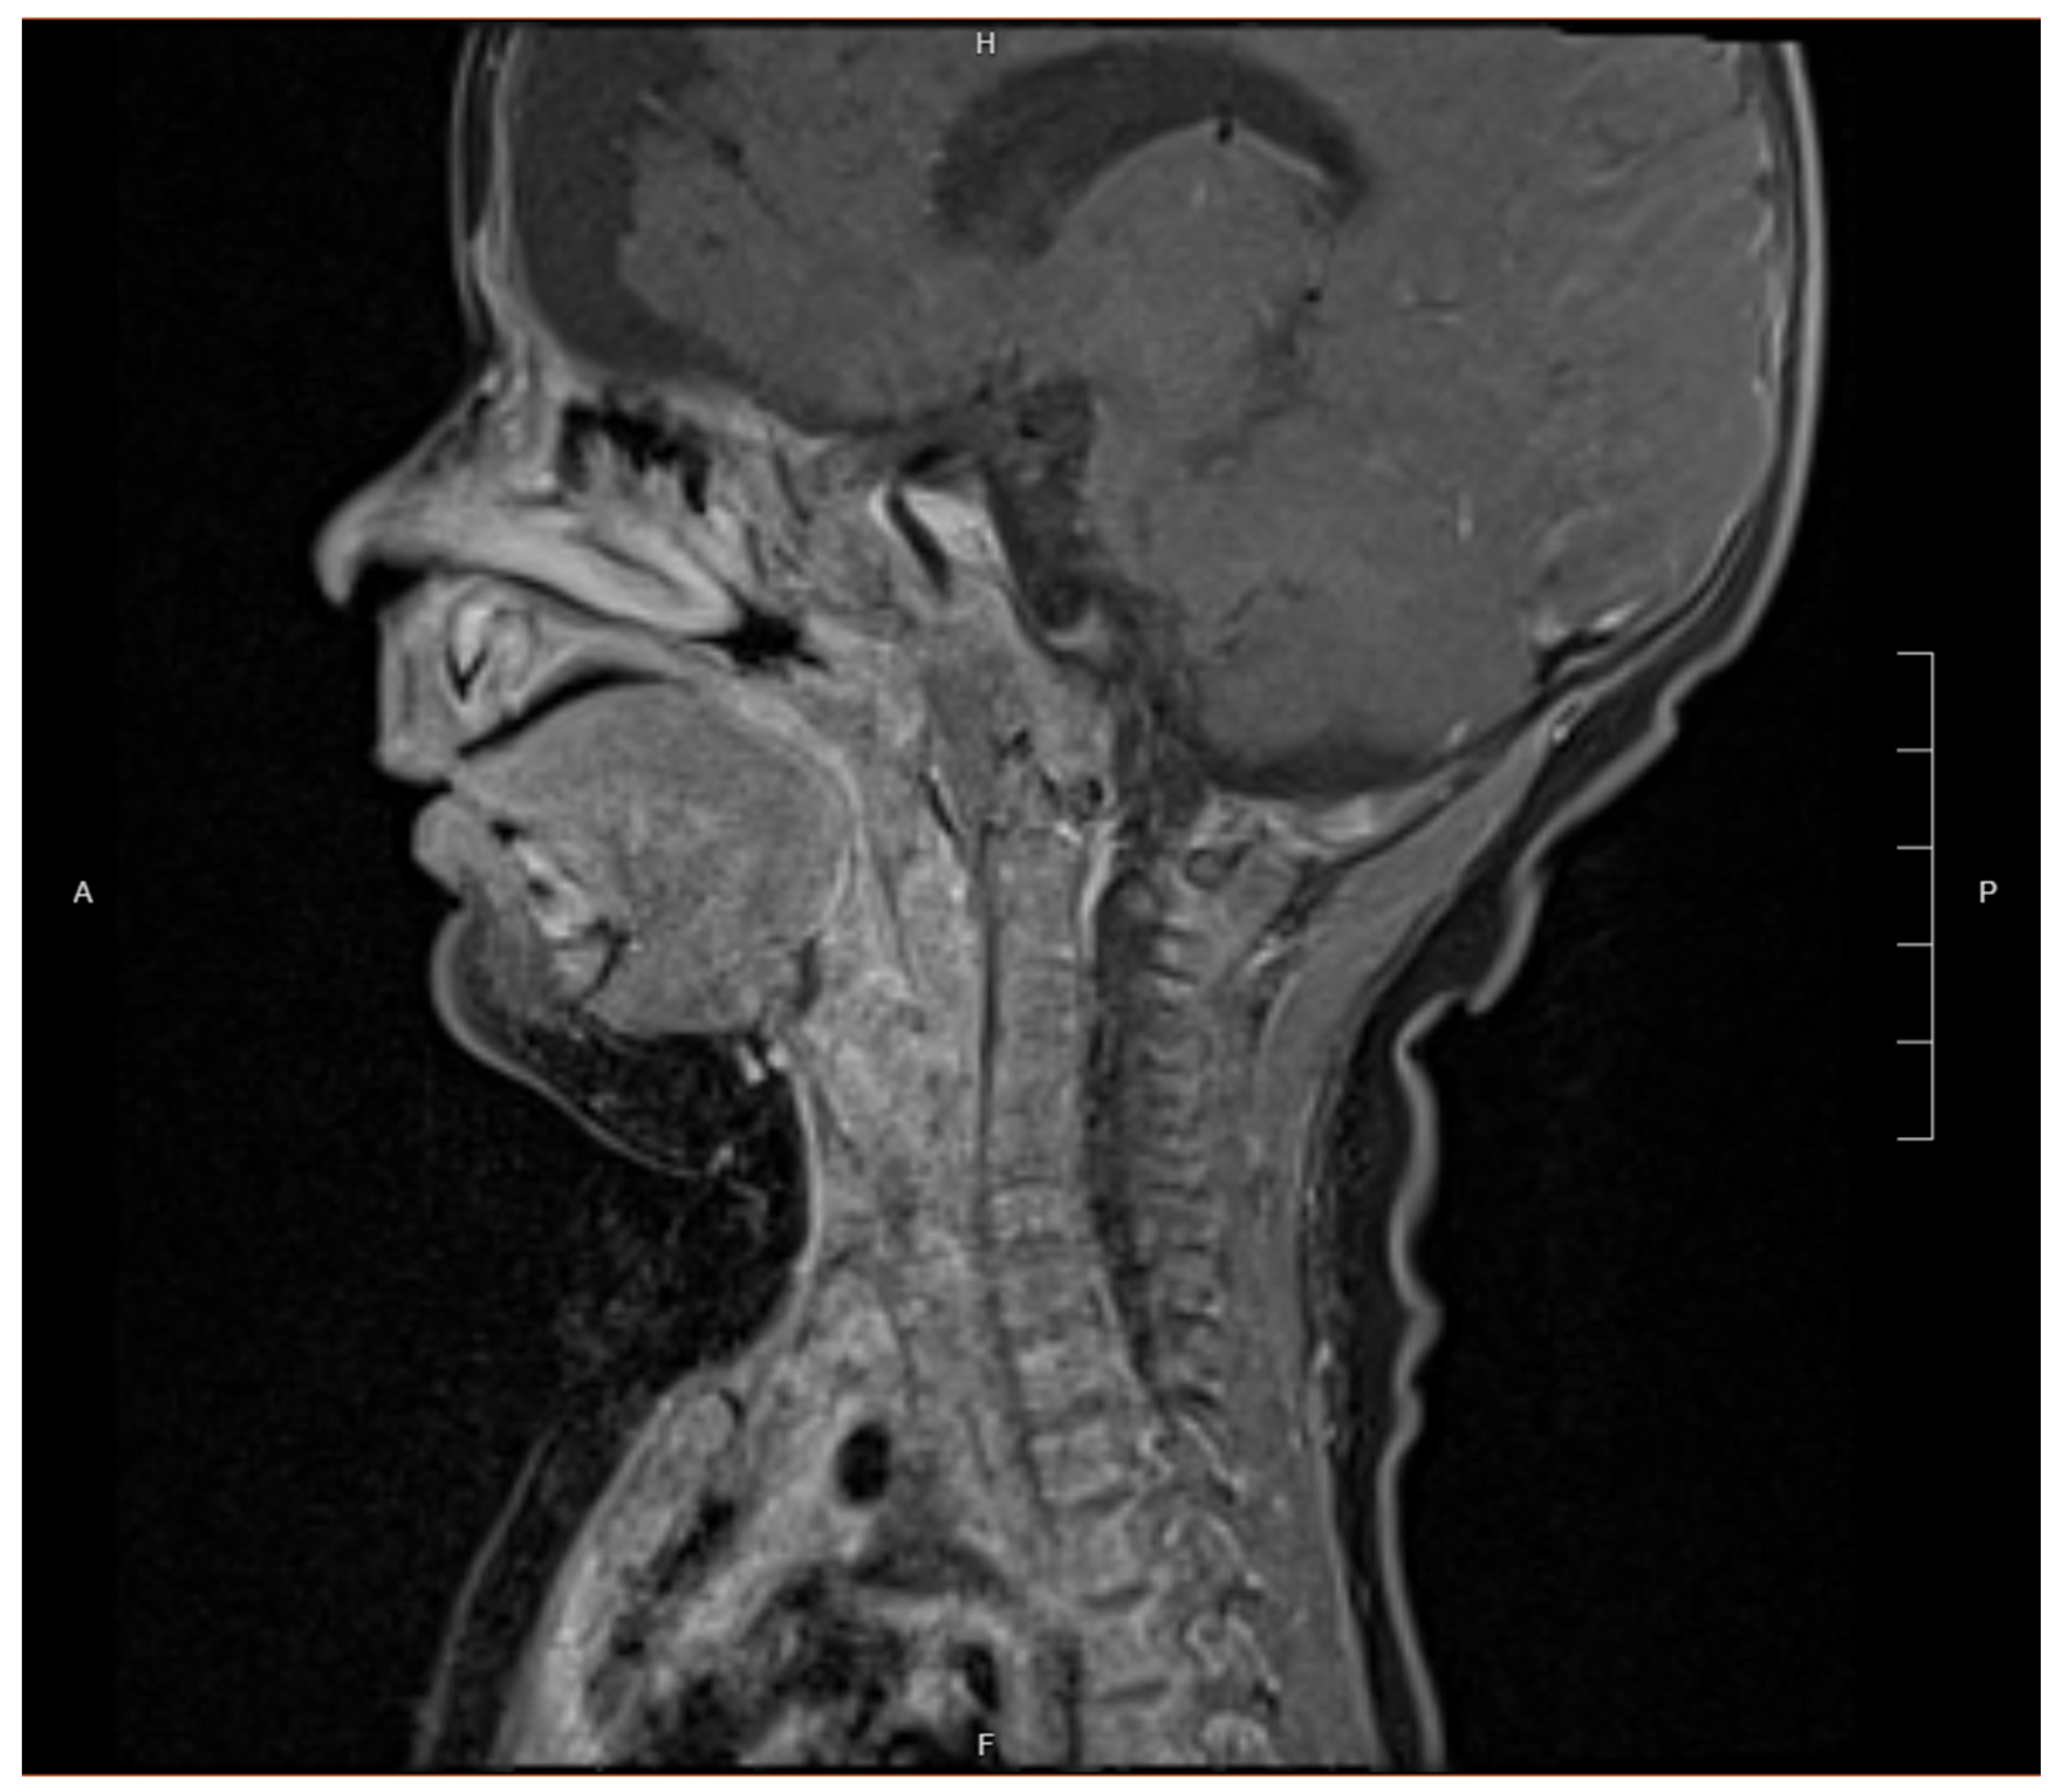

2. Case Presentation